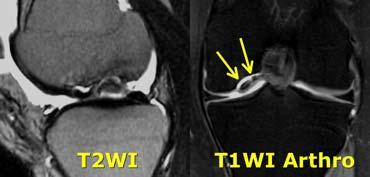

Viêm xương sụn bóc tách

Chẩn đoán Viêm xương sụn bóc tách thường được thực hiện trên X-quang.

Câu hỏi đặt ra khi chụp MRI là tổn thương ổn định hay không ổn định.

Ca lâm sàng bên trái là không ổn định vì hai lý do:

– Các nang nhỏ ở nền tổn thương (mũi tên đỏ)

– Quan trọng hơn là có dịch ở nền tổn thương (mũi tên xanh)

Lưu ý rằng lớp dịch này khác với AVN, nơi dịch nằm giữa sụn và xương.

Viêm xương sụn bóc tách không ổn định. Dấu hiệu duy nhất có giá trị để chẩn đoán OD không ổn định là dịch (mũi tên vàng), không phải phù tủy hay gián đoạn bề mặt xương sụn (mũi tên xanh lá).

Các dấu hiệu không có giá trị trong việc phân biệt OD ổn định và không ổn định bao gồm:

– Phù tủy xương (có thể gặp trong cả hai trường hợp)

– Gián đoạn bề mặt xương sụn.

Vì vậy, ca lâm sàng bên trái là không ổn định vì có dịch ở nền tổn thương.

Ca lâm sàng bên trái cho thấy viêm xương sụn bóc tách với phù tủy xương và gián đoạn bề mặt xương sụn.

Tuy nhiên, vì không có dịch, chúng ta không thể xác định đây là tổn thương ổn định hay không ổn định.

Trong phẫu thuật, tổn thương viêm xương sụn bóc tách được xác nhận là ổn định.

Trong những trường hợp không thể xác định tổn thương ổn định hay không ổn định, chụp MRI khớp có thuốc tương phản từ (MR-arthrogram) rất có giá trị.

Chúng ta tìm kiếm dấu hiệu Gadolinium thấm vào xung quanh tổn thương xương sụn.